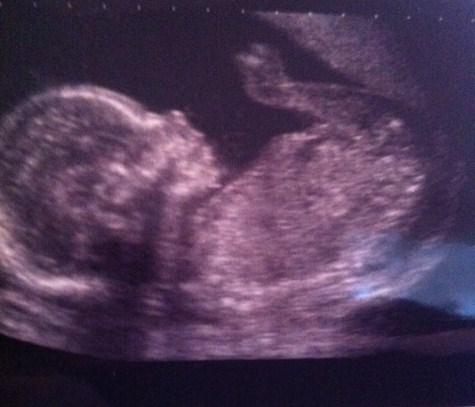

here are two 12 week scan pictures where the nub looks different in both, just for fun i was wondering what gender people thought the little one is based on the skull and nub theories.

xAttachment 3020Attachment 3021